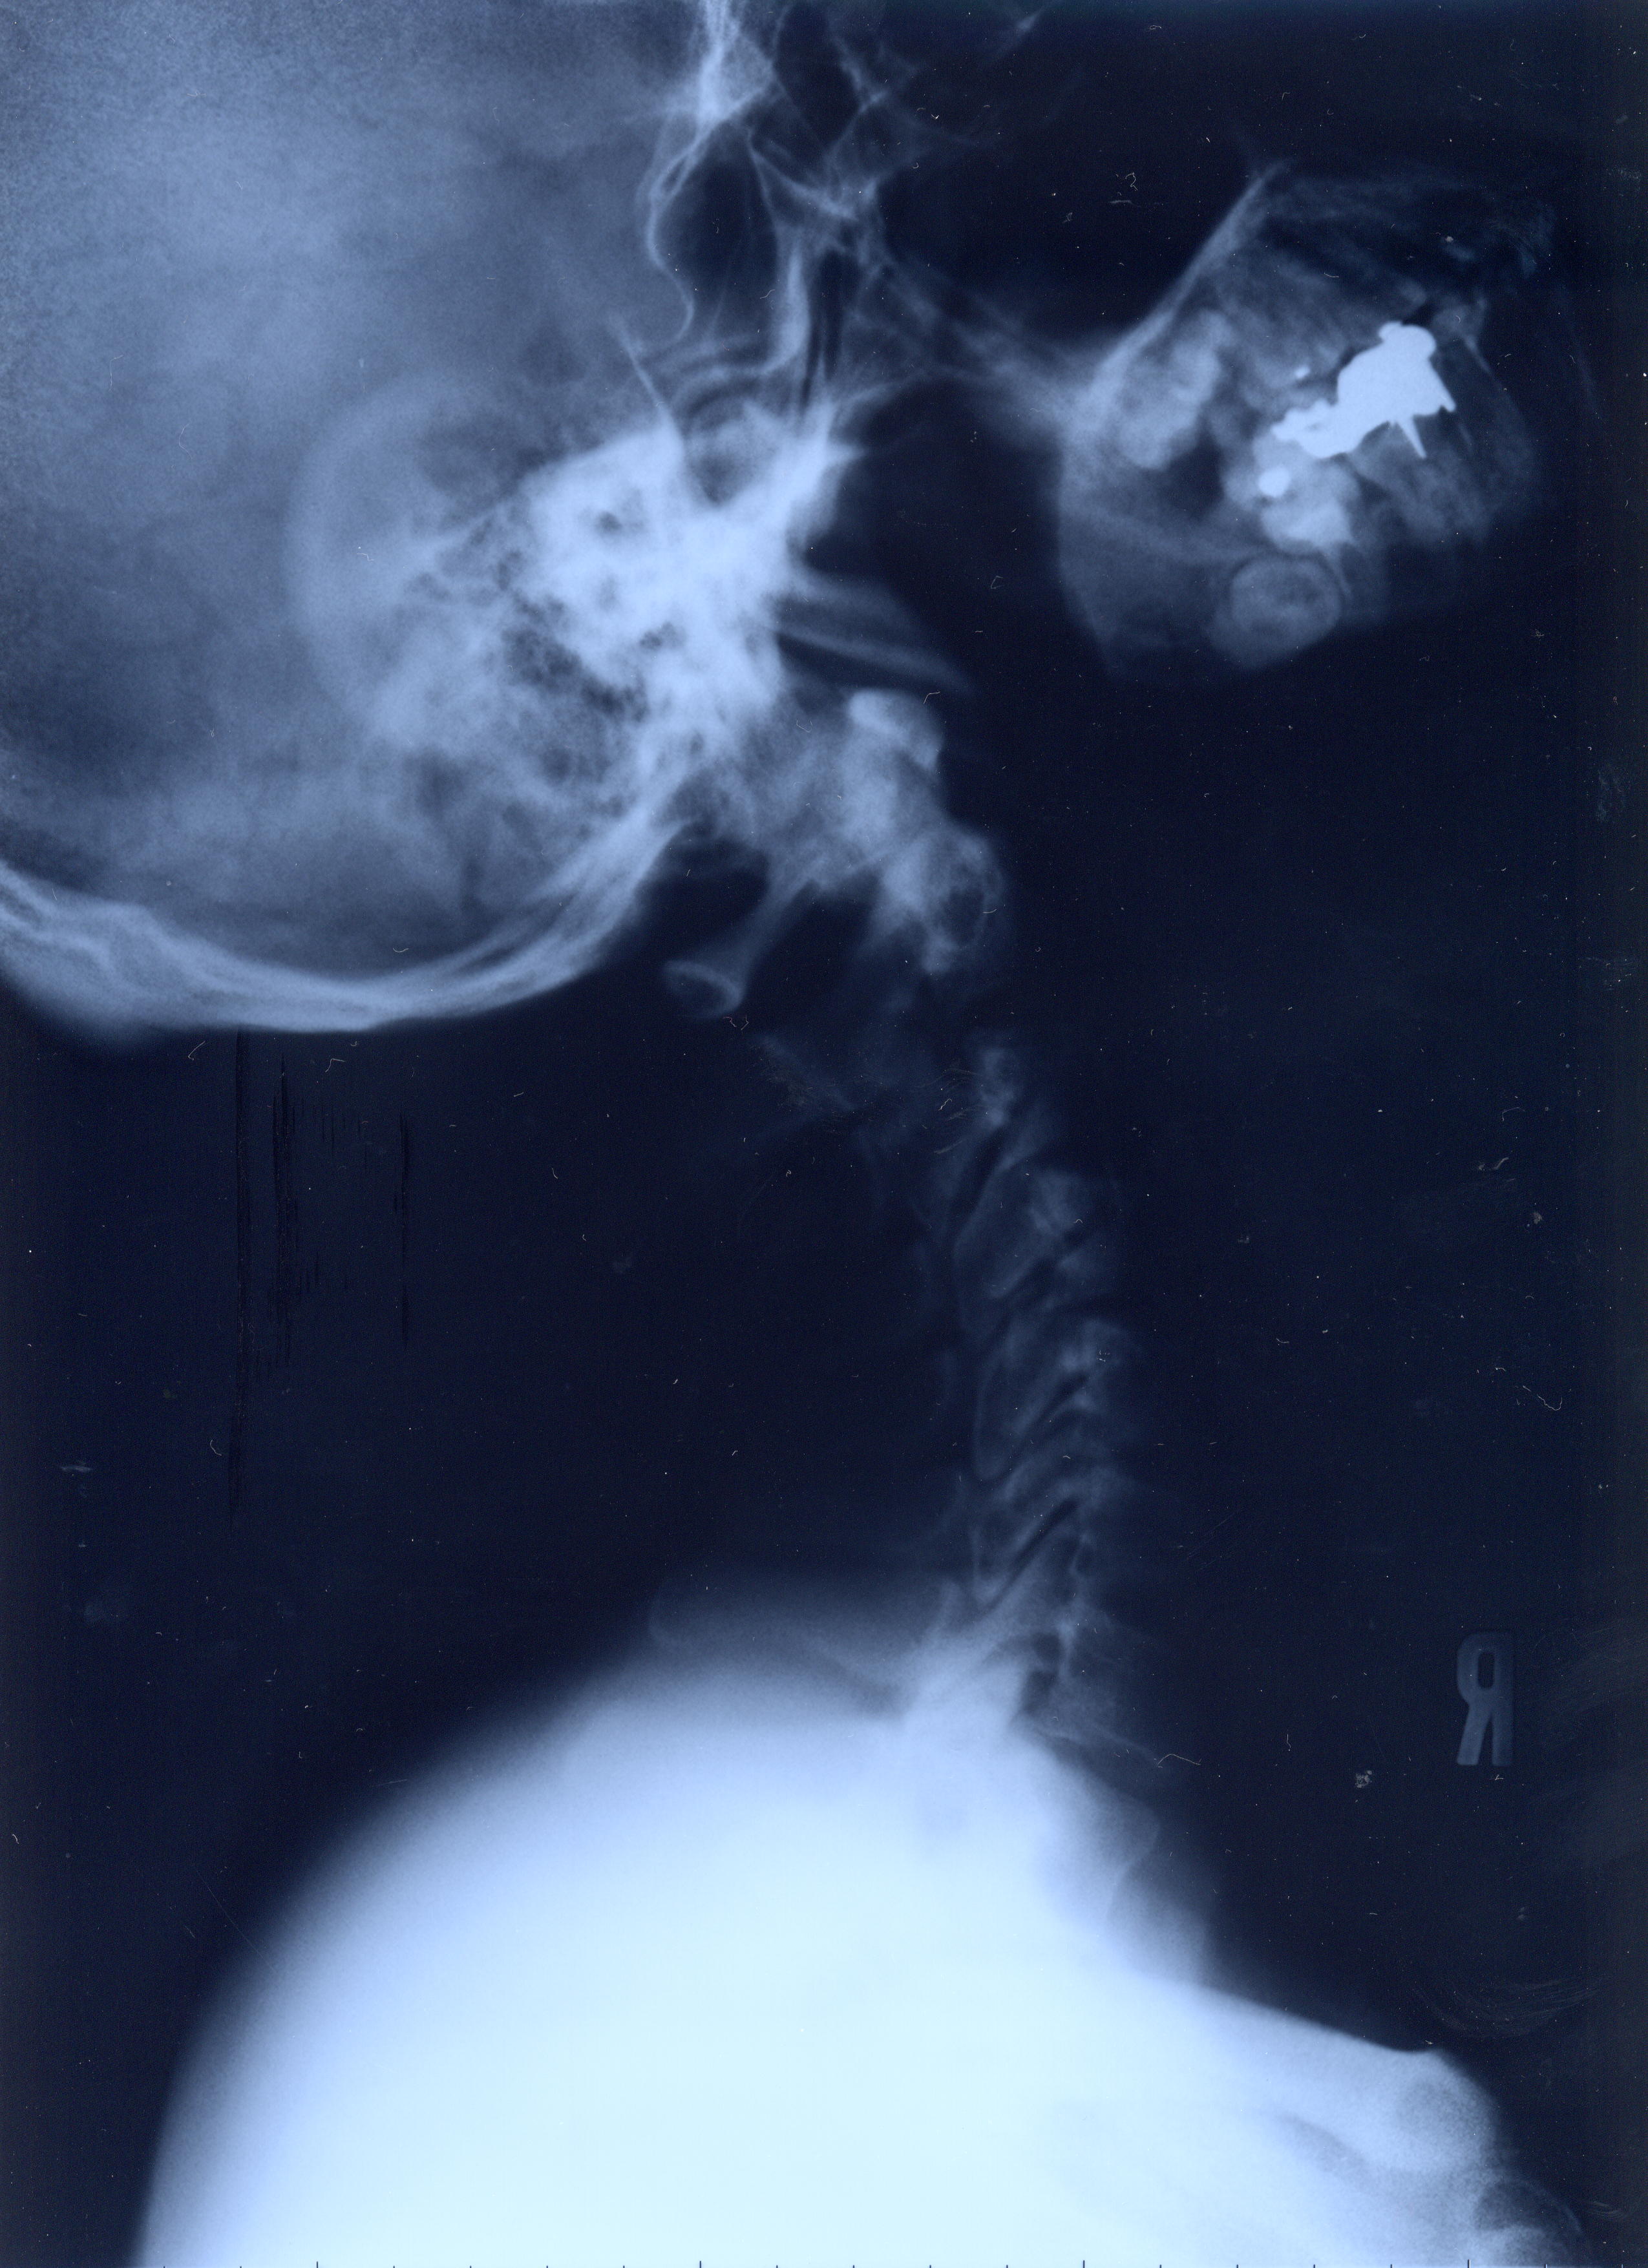

@@Ž„‚Μ”wœ‚Μ‚wόŽΚ^‚Ε‚·@@˜‚ͺ’Ι‚­‚Δ’Ι‚­‚āII@2002/1/22ŽB‰e

‚SDŽρ‚̐³–ʁ@@Šg‘ε